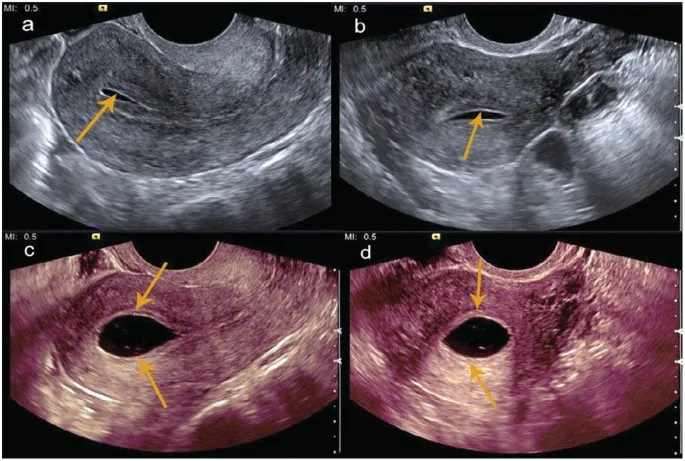

Nowoczesne Sono-HSG (HyCoSy): Dlaczego USG i pianka są uważane za delikatniejszą opcję?

Sono-HSG, znane również jako HyCoSy (Hysterosalpingo-Contrast Sonography), to metoda, którą osobiście bardzo cenię. Zamiast promieniowania rentgenowskiego, wykorzystuje się tu ultrasonografię, a zamiast gęstego kontrastu specjalną piankę lub sterylną sól fizjologiczną z pęcherzykami powietrza. Dzięki temu badanie jest znacznie bezpieczniejsze (brak promieniowania) i, co najważniejsze dla wielu pacjentek, uważane jest za mniej bolesne. Pianka jest delikatniejsza i łatwiej przepływa przez jajowody. Koszty Sono-HSG w prywatnych klinikach w Polsce wahają się zazwyczaj od 600 do 1200 zł, co jest inwestycją w większy komfort i bezpieczeństwo.